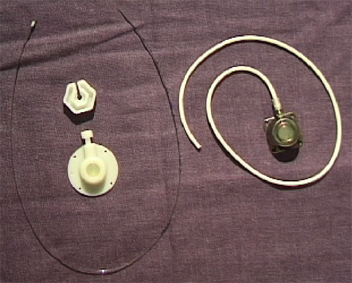

-Tunnelierte Katheter einlumig dünn aus Silikon für TPN, mehrlumig dick aus Silikon für Apherese, Dialyse und Knochenmarkstransplantation.

-Ports für gelegentliche Anwendung über langen Zeitraum (Chemotherapie).

Tunnelierung und Port

Langzeitkatheter und Portkatheter werden von der Punktionsstelle supraklavikulär 4 - 6 cm bis zum Thorax tunneliert.

Da tunnelierte Katheter eine fixe Länge haben, muß die Austrittsstelle exakt vermessen werden, dass einerseits die Katheterspitze im Vorhof bzw. der Vena cava superior liegt, andererseits der Tefloncuff mindestens 2 cm von der Austrittsstelle entfernt im Tunnel.